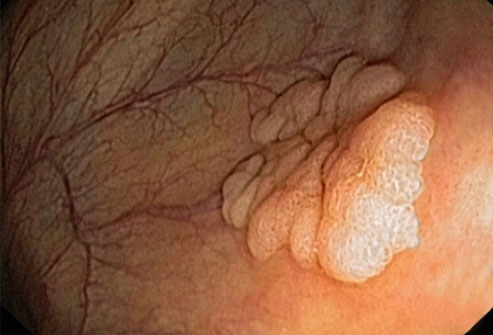

宫颈癌

通过常规宫颈涂片,宫颈癌(如图)很容易预防。宫颈是子宫和阴道之间的狭窄通道。宫颈涂片能发现宫颈上的异常细胞,并将它们在癌变前移除。宫颈癌的主要原因是人类乳头瘤病毒(HPV),一种性传播感染。

大多数结肠癌是大肠内壁生长的息肉发展而来的。息肉可能是也可能不是癌细胞。如果息肉属于癌细胞,那么癌细胞可能会扩散到身体的其他部位。在息肉癌变前就将其移除,可以完全预防结肠癌。

结直肠癌筛查

结肠镜检查是一种常见的结直肠癌的筛检方法。医生会使用结肠镜进行检查。如果发现息肉,医生可能在检查过程中将其移除。另一种测试是更灵活的乙状结肠镜检查,这种检查只会检查结肠下部。如果你的风险水平属于平均态势,筛查通常从50岁开始进行。